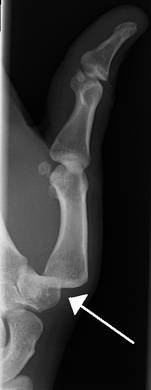

A traumatic dislocation of the tibiotarsal joint of the ankle with distal fibular fracture. Open arrow marks the tibia and the closed arrow marks the talus.

X-rays are usually taken to confirm a diagnosis and detect any fractures which may also have occurred at the time of dislocation. A dislocation is easily seen on an X-ray.[8]